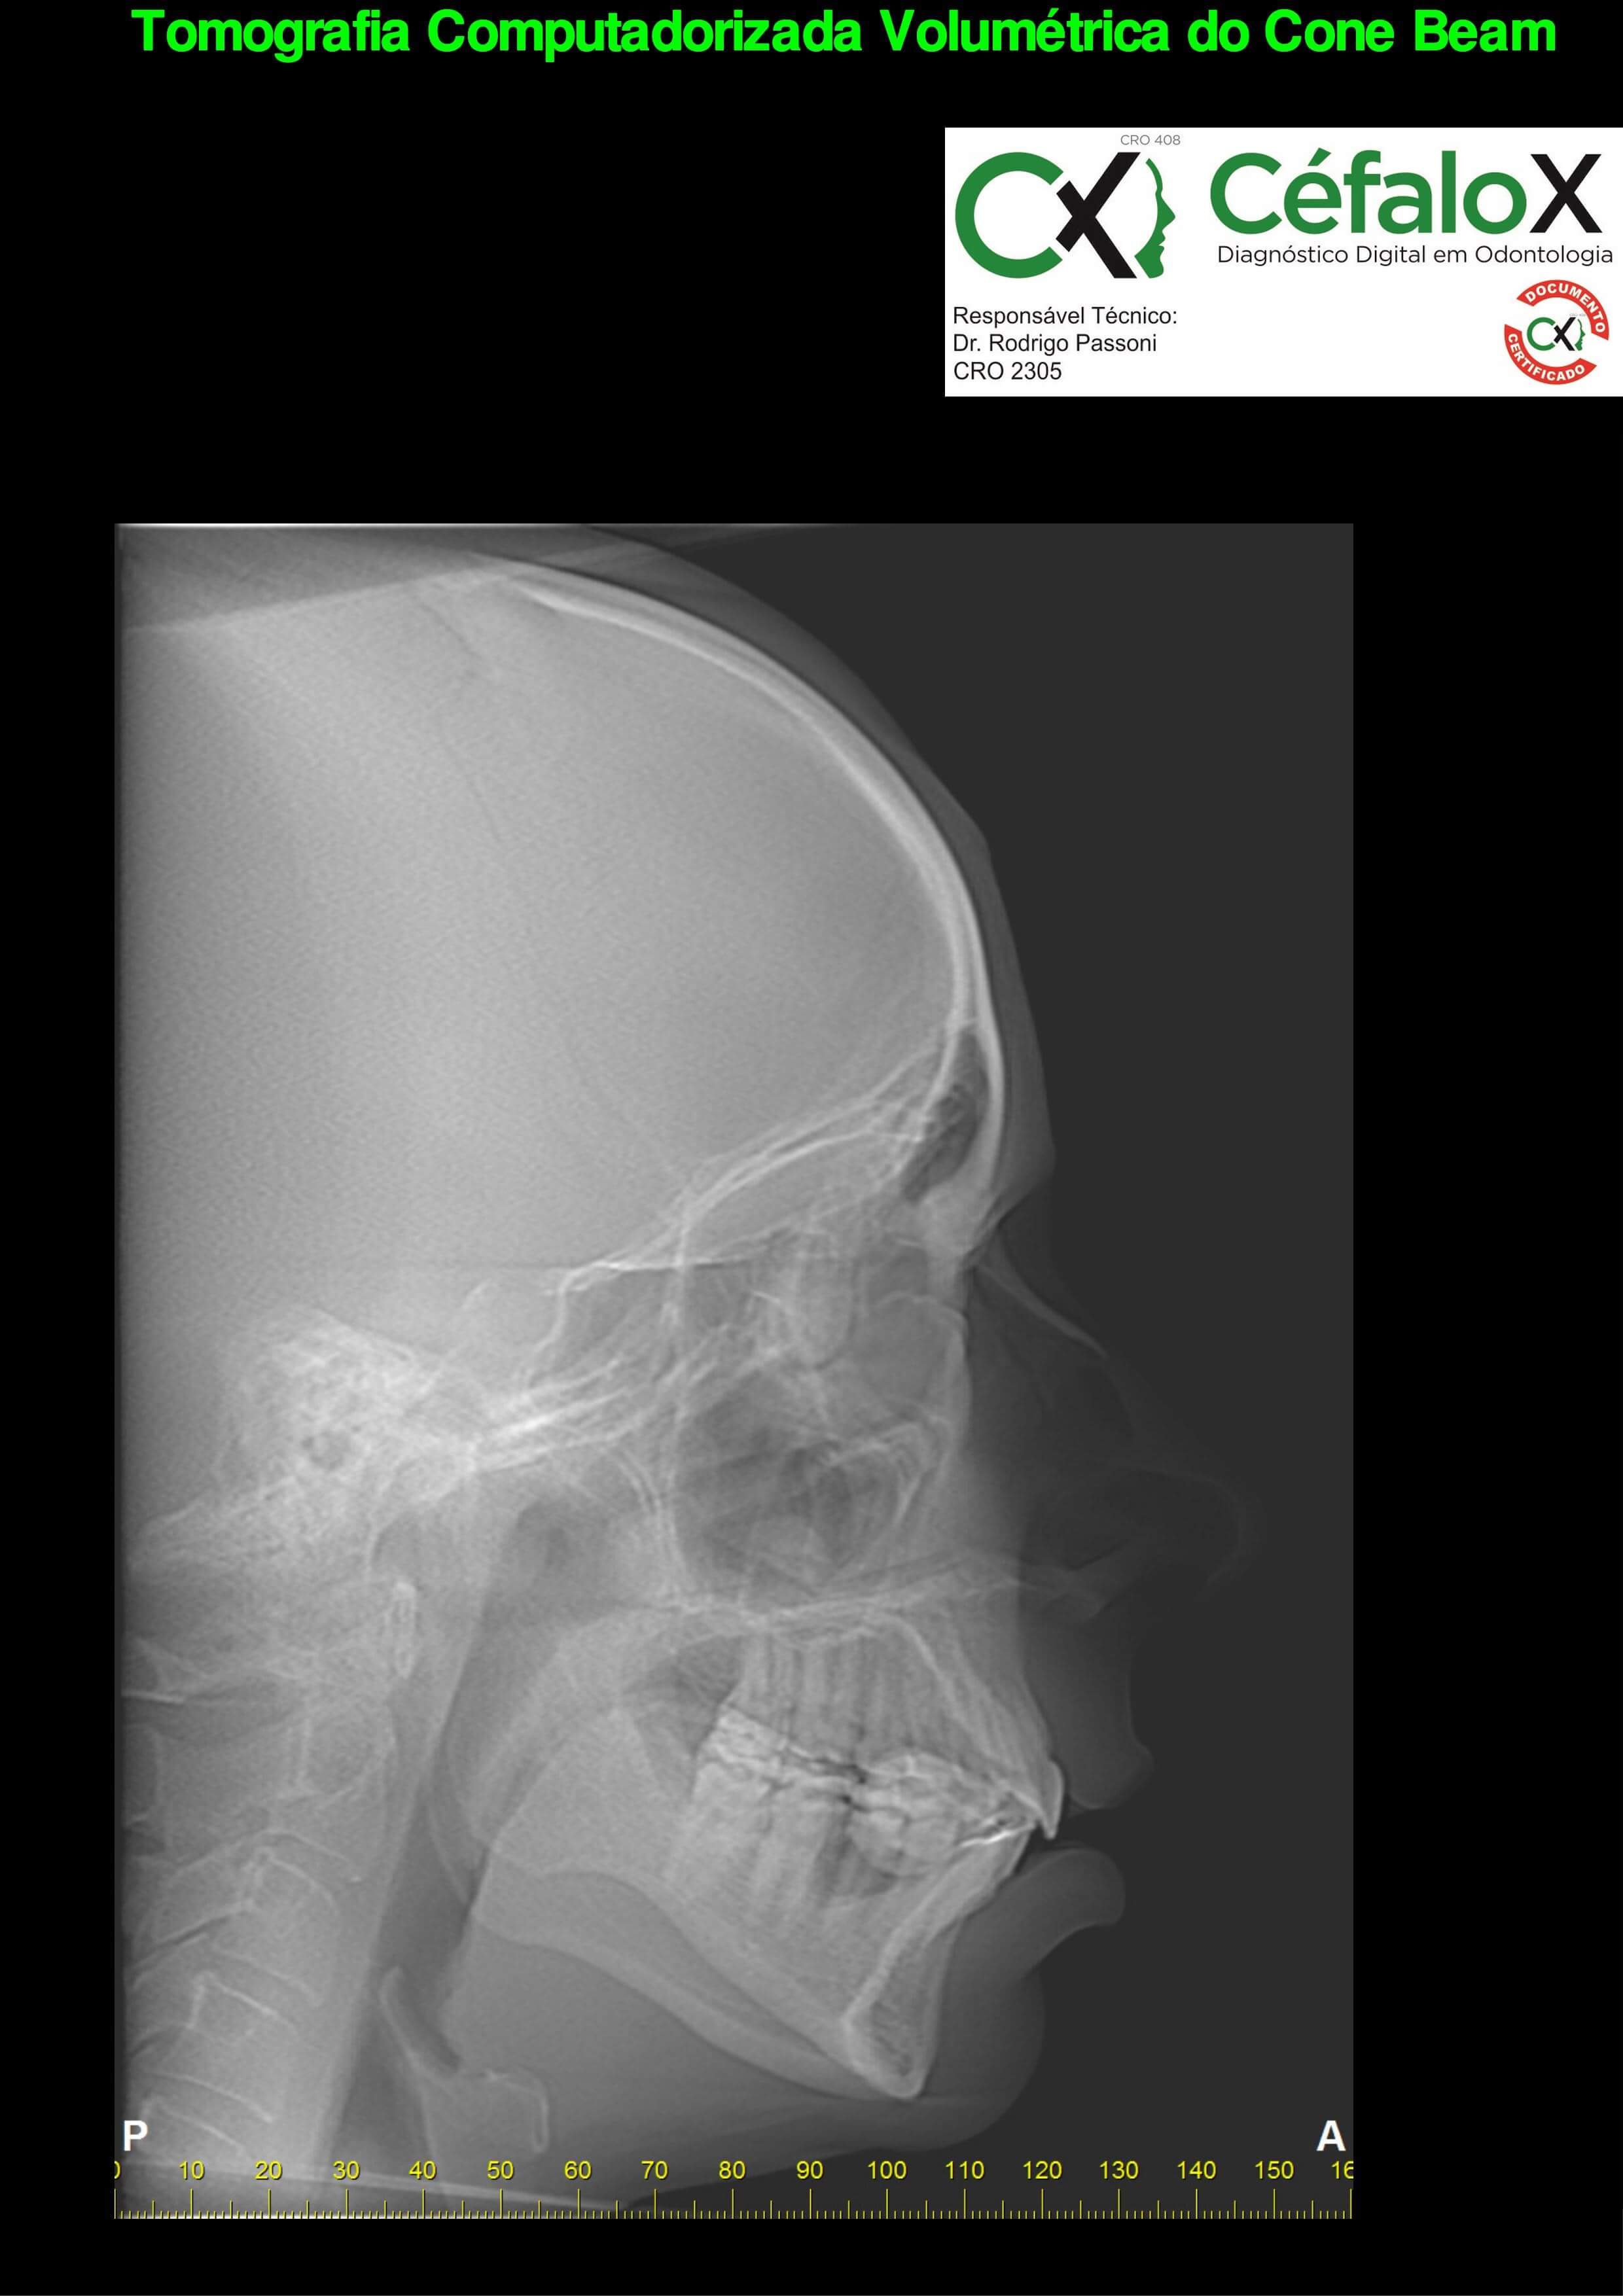

TC de face (do Hióide à Glabela), reconstrução 3D do tecido ósseo, radiografia panorâmica, telerradiografia lateral com traçado, cortes transversais e axial de maxila e mandíbula e arquivo DICOM- entregue em pasta de Pvc.

TC de face (do Hióide à Glabela), reconstrução 3D do tecido ósseo, radiografia panorâmica, telerradiografia lateral e frontal com traçado, cortes transversais e axial de maxila/mandíbula e arquivo DICOM – entregue em pasta de Pvc.

TC de face (do Hióide à Glabela), reconstruções 3D do tecido mole/ósseo/vias aéreas, radiografia panorâmica, telerradiografia lateral e frontal com traçado, cortes transversais e axial de maxila/mandíbula, ATM e arquivo DICOM – entregue em pasta e caixa de Pvc.